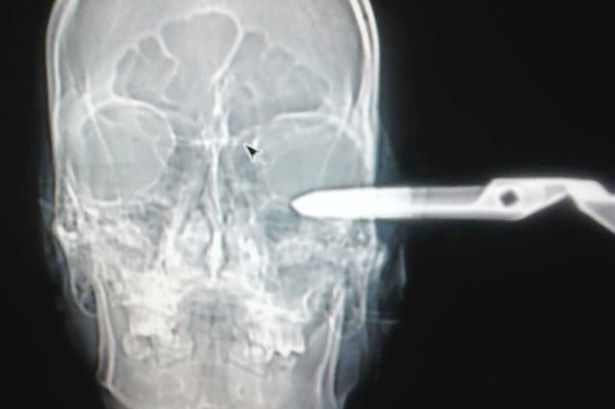

Jonas Acevedo Monroy in realtà ha rischiato molto: era stato pugnalato nel lato superiore sinistro del cranio e le forbici erano penetrate nel lobo parietale del cervello. “E ‘fortunato ad essere vivo” ha aggiunto il portavoce della struttura ospedaliera. La polizia, dopo essere venuta a conoscenza della storia, ha arrestato l’uomo responsabile dell’aggressione con le forbici.